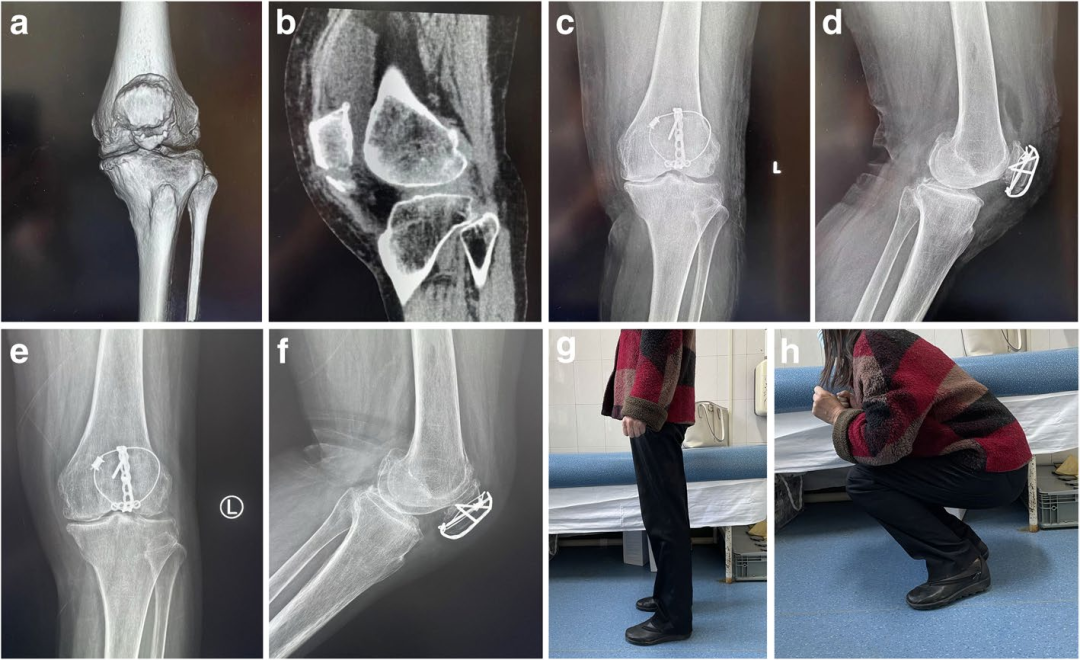

图2. 术中复位。

a-b术前CT检查。

c复位前拍摄的术中图像。

d复位后的术中图像。

e-f复位后的术中c型臂透视。

图3. 对照组和实验组患者复位前后的比较。

a - f : 38岁,男性,入院前3小时因摔伤导致骨折入院。a-b术前CT检查矢状面。c-d术前冠状面CT检查。e-f术后x线片。

g-l:一名65岁女性,入院前5小时因跌倒导致骨折。g-h术前矢状面CT检查。i-j术前冠状面CT检查。k-l术后x线片。

扎骨针怎么装髌骨下极粉碎骨折怎么办?7种固定技术详解与术式选择_https://www.jmylbn.com_新闻资讯_第27张

图4. 对照组和实验组患者术后骨折愈合情况比较a-d。患者男,42岁,入院前4 h因跌倒致骨折入院。

a.术前x线侧位片

b.术后x线侧位片

c.术后12周随访x线侧位片。患者女,38岁,入院前3 h因跌倒致骨折入院

d.术前矢状面CT检查

e.术后x线侧位片

f.术后12周随访x线侧位片